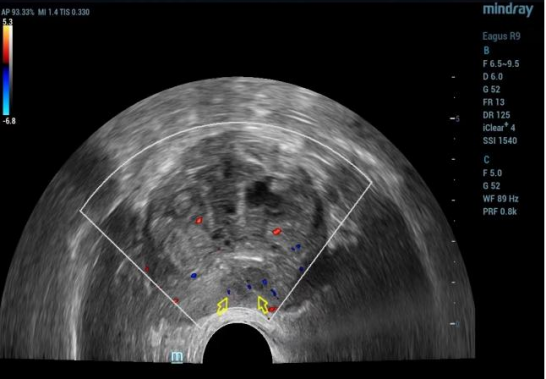

(图1为MRI发现前列腺外周带可疑结节;图2为超声双平面探头下前列腺对应区域可疑结节的低频声像)

术中会将前列腺分为10个区域,在直肠超声实时双平面引导下,用仅直径1.2mm细针在前列腺组织内提取组织。

对于可疑前列腺肿瘤患者一般都会进行磁共振检查,超声图像结合磁共振图像,将两者进行结合,再给出明确的穿刺靶目标,做到个性化诊治,为后续治疗方案提供依据。